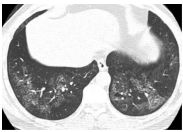

17. 50 y/o Female, Progressive dyspnea and cough for months.